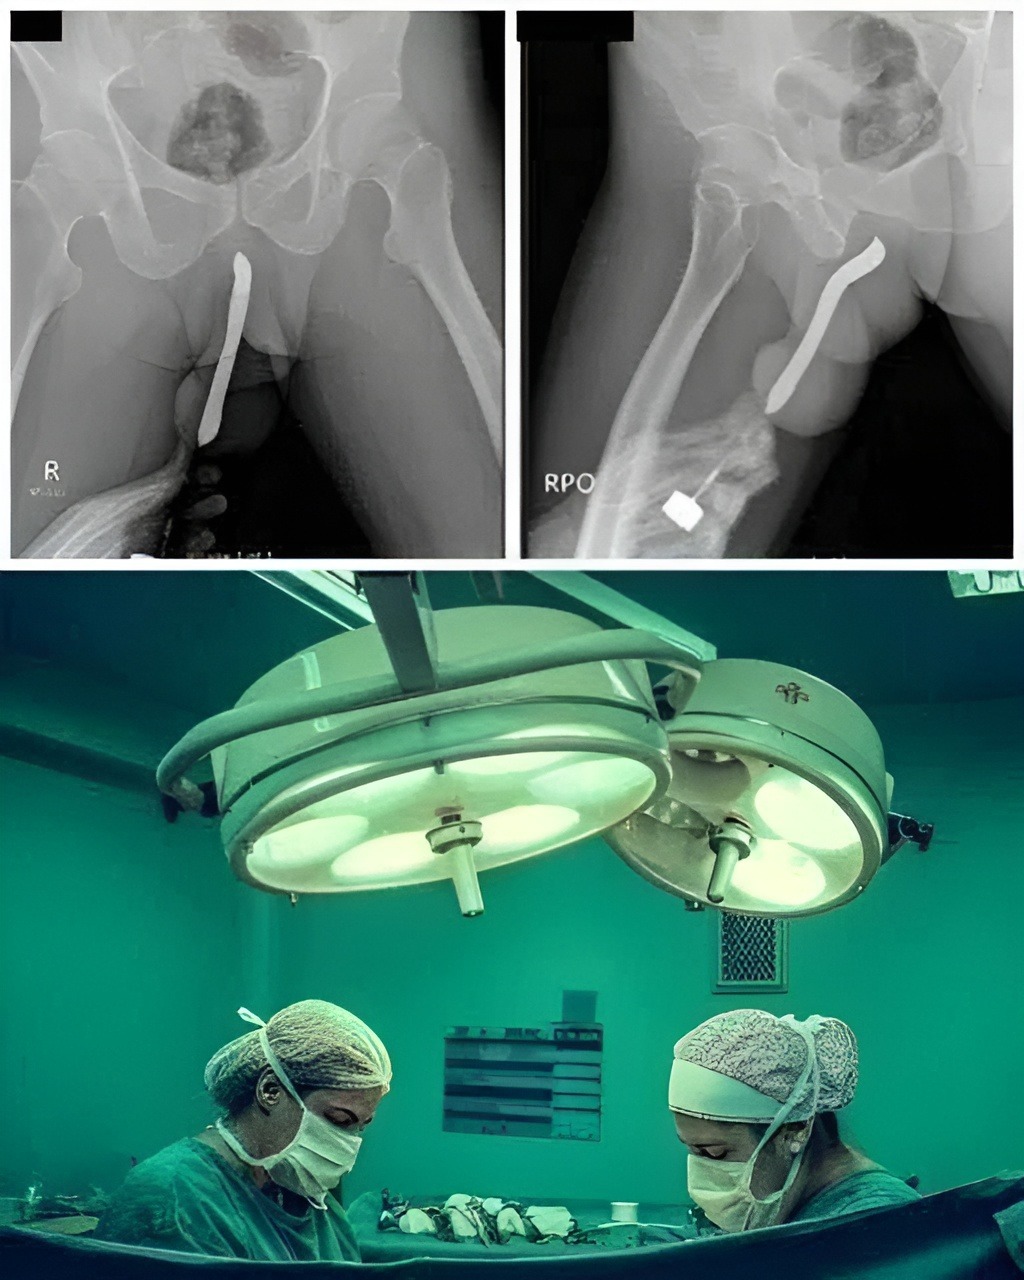

Once she arrived at the emergency room, doctors began running tests. Because the cause of her pain was unclear, they ordered a scan to rule out internal bleeding or abdominal complications. What they found instead was the household tool lodged deeper inside her body than she realized — not due to intentional usage, but due to the angle, force, and the completely accidental way it had slipped.

The medical team immediately prepared for a controlled procedure to remove the object safely, as improper handling could worsen the injury. Fortunately, they were able to retrieve it without major surgical intervention, and there were no long-term complications.